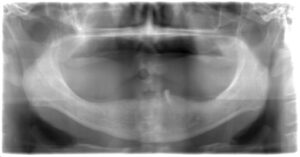

普段から通院していただいている優しい患者様に許可をいただいたので写真を掲載します。

もともと下の歯が1本だけ残った状態の上に総入れ歯(総義歯)を使用していただいていたのですが、安定感をより増やすために、数年前に残っている歯と義歯にアタッチメントとよばれる器具を設置しました。

下の歯の総義歯は上に比べると安定感がないケースが多く見られます。上の総義歯が安定するときは特にそう感じるかもしれません。

そこでかねてからお話をしていたインプラントを2本埋入し、残っている歯の負担軽減と、義歯の安定を図る計画を立てました。